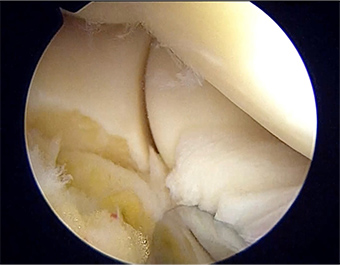

外側上顆炎(テニス肘)

肘の外側に痛みを生じる疾患で、手首を伸ばす筋肉が骨に付着する部分の腱が繰り返し引っ張られて炎症や変性を起こすことが原因です。物を握ったり捻ったりする動作で痛みが強くなります。多くは保存療法で改善し、ストレッチ、注射などが用いられます。慢性化した場合には、関節鏡視下で滑膜切除と腱起始部の再縫合を行います。靭帯断裂まで至っている例に関しては靭帯再建を行います。

症例 40代 男性 関節鏡所見 腕橈関節内の滑膜ひだを切除している